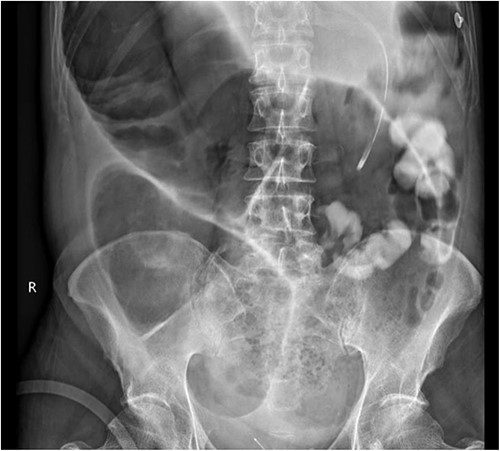

Intraoperatively, there was massively dilated caecum and transverse colon, with a large caecum serosal tear and multiple transverse colon serosal tears as well as a contained perforation at the hepatic flexure. The small bowel was nondilated, and there was general tapering of the left colon. A subtotal colectomy with end ileostomy was performed. Histopathology confirmed ischaemic colitis with ulceration, perforation, and peritonitis as well as a positive Congo red stain consistent with extensive AL involving blood vessels, bowel wall, and fat (Fig. 4).

Surgical pathology of tissue. (a) Arteries within the bowel wall show marked circumferential thickening by amorphous eosinophilic material consistent with amyloid. H&E, original magnification ×200. (b) Congo red stain showing positive staining within the blood vessel wall consistent with AL. Congo red, original magnification ×200. (c) Congo red stain showing green birefringence under polarized light. Congo red with polarisation, original magnification ×200.

The gold standard for diagnosing AL requires tissue biopsy of the affected organ with Congo red staining, with a positive result confirming the diagnosis. This is typically referred to as the ‘apple green birefringence’ in polarized light, as demonstrated in Fig. 4 [2].